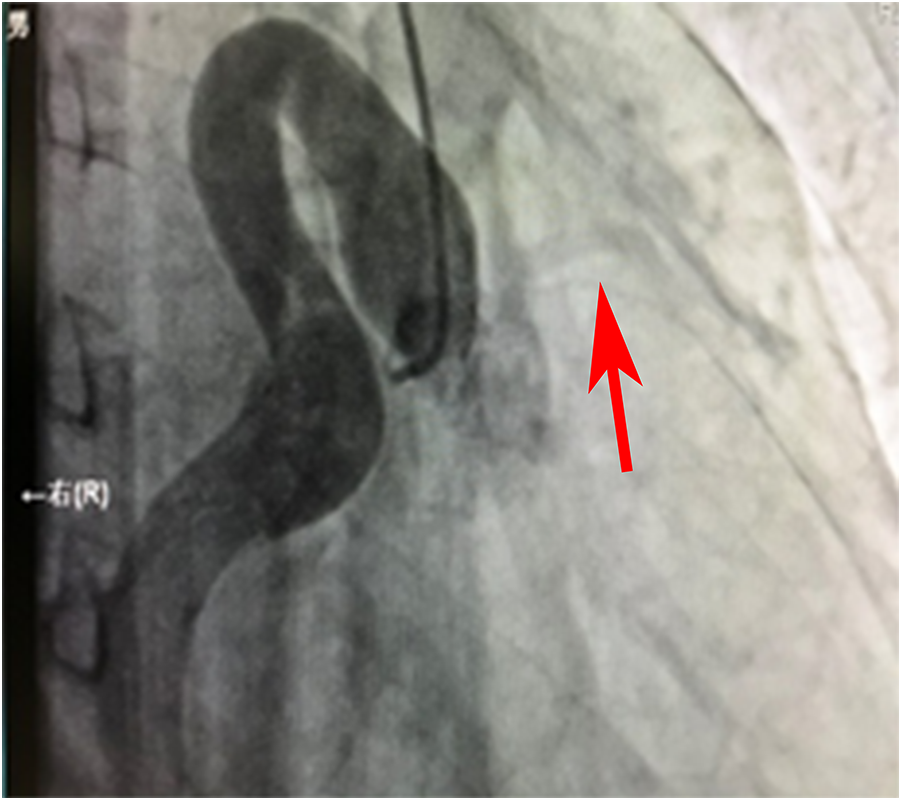

Figure 1

Angiographic image of the ostium and proximal segment of the RCA.

Figure 1 shows that the right coronary artery opens into the aorta and is cystic throughout the entire process. A small left coronary artery can be seen on the left side (red arrow).